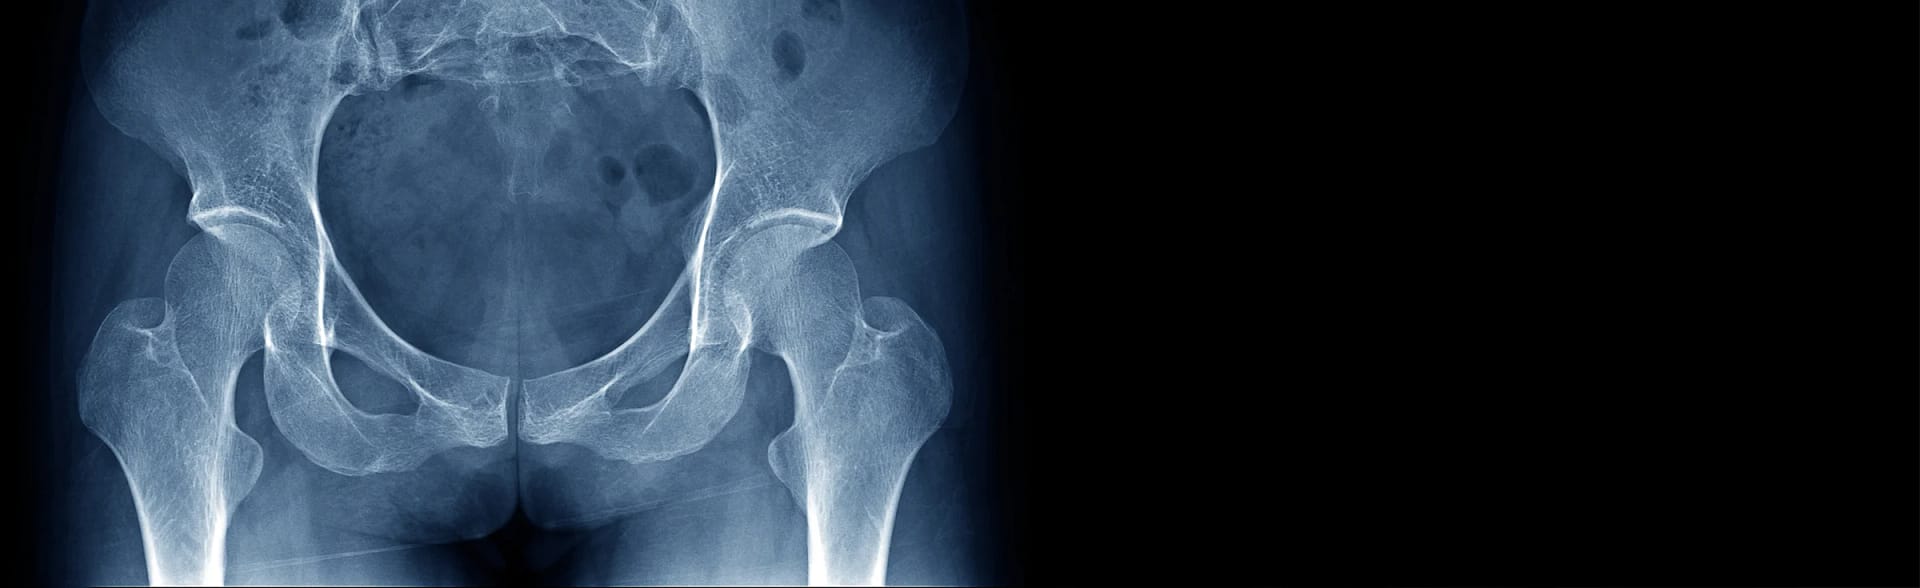

Hip resurfacing is an advanced surgical technique that can be used to treat painful arthritis. It has received a resurgence in media attention due to professional tennis star Any Murray and NBS basketball player Isaiah Thomas both undergoing hip resurfacing surgery and successfully returning to competitive professional sports. Unlike traditional total hip replacement surgery, hip resurfacing preserves more bone and provides an excellent alternative for younger, active patients who seek a durable and long-lasting solution to hip problems.

Hip resurfacing involves carefully trimming the damaged femoral head surface and capping it with a smooth metal or ceramic covering, promoting a more natural range of motion and reducing the risk of dislocation by allowing an enhanced range of motion. Hip resurfacing implants are typically designed to withstand the rigors of an active lifestyle.